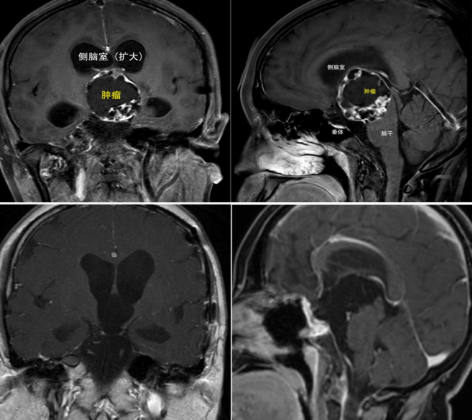

术前(上)、术后(下)头部核磁共振扫描图像

经过详细的手术计划和预案准备,2023年9月2日,手术按计划进行,姜曙教授进行指导、周培志副教授进行操作。手术通过神经内镜经鼻腔入路、经过极为狭小的神经、血管间隙深入颅脑中心。术中发现肿瘤与周围重要的神经粘连严重,团队借助精细器械,凭借娴熟的操作一点点剥离肿瘤,最终将原来开颅才能切除的肿瘤通过鼻腔进行了完整切除。

因颅咽管瘤有一定的复发概率,黄女士还需长期复诊随访。今年5月底,术后8个月,黄女士术后复查核磁共振,未见肿瘤残留和复发踪影。她和家人还专门带着女儿来感谢华西医生。